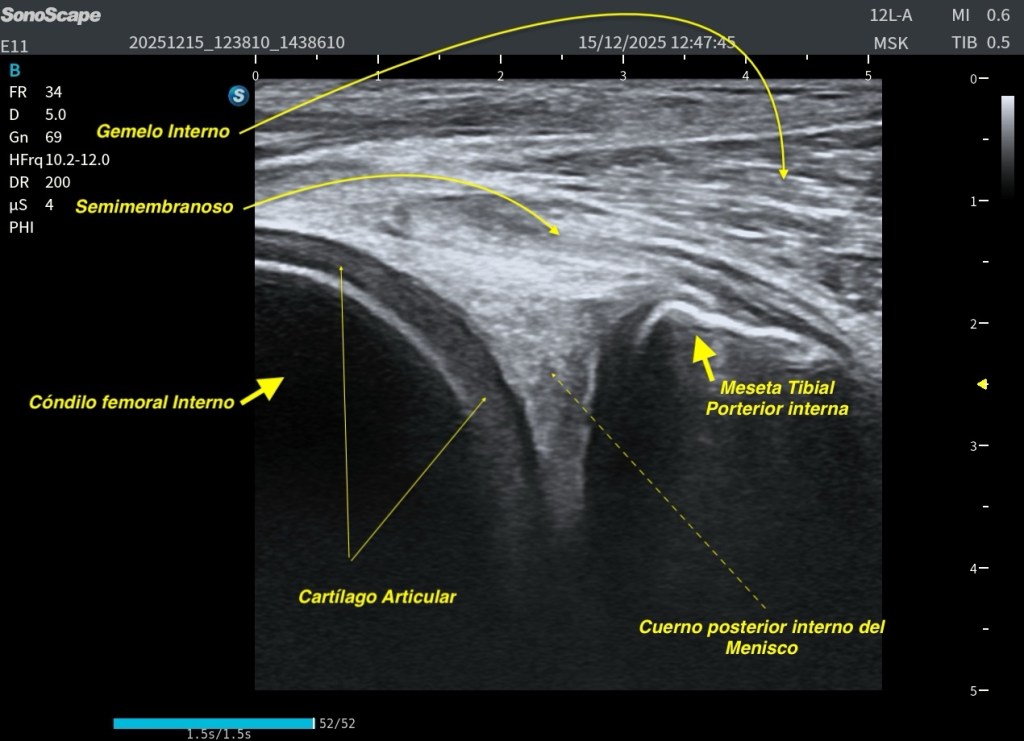

Conseguir una imagen como la de la imagen 3, donde se visualizan las raíces del plexo braquial en su salida cervical lateral, no siempre es fácil, pero tiene un gran valor docente. Esta vista permite comprender la disposición de las raíces en tres niveles:

Raíz superior (C5–C6)

Raíz media (C7)

Raíz inferior (C8–T1)

Si continuamos explorando en el eje sagital de las raíces nerviosas, progresivamente vamos a desplazarnos hacia una región donde comienzan a aparecer los músculos escalenos, que son la referencia anatómica clave en este nivel.

En este punto, es fundamental realizar una maniobra técnica importante: girar el transductor hacia un plano transversal oblicuo, adaptado al espacio interescalénico. Este ajuste nos permite visualizar de forma óptima los troncos del plexo braquial, situados entre el escaleno anterior y el escaleno medio.